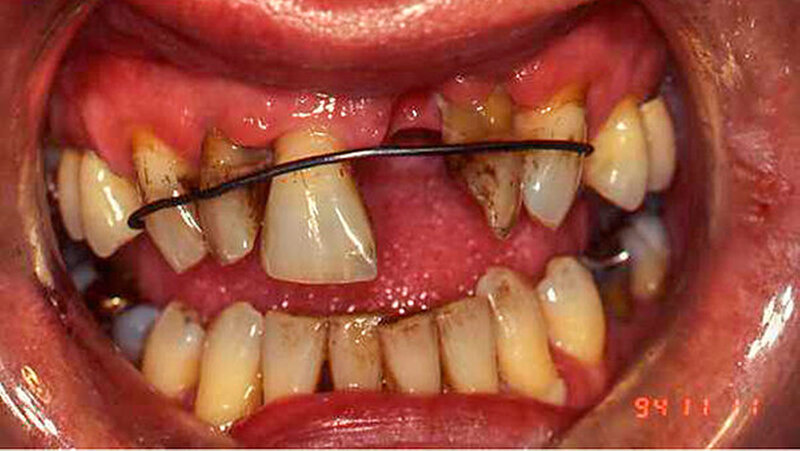

Festgezurrt mit Blumendraht

Dieser Fall wurde eingereicht von Dr. Wilfried Forschner, Köhlestrain 86, in 88400 Biberach

"Die Ausnahmefälle kommen Freitagabend kurz vor Praxisschluss", heißt es oft in Fortbildungen. Genauso ist es. Und wenn nicht, sind es Fälle, die auch nach der Arbeit im Gedächtnis bleiben.